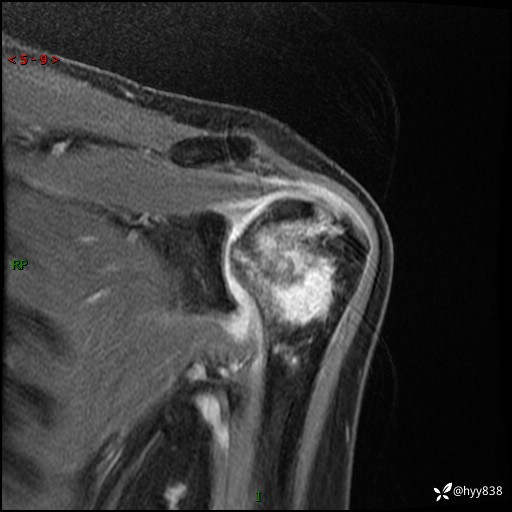

肱骨MRI平扫(axi T1WI+cor T2WI-fs)+CE-fs(COR+SAG)